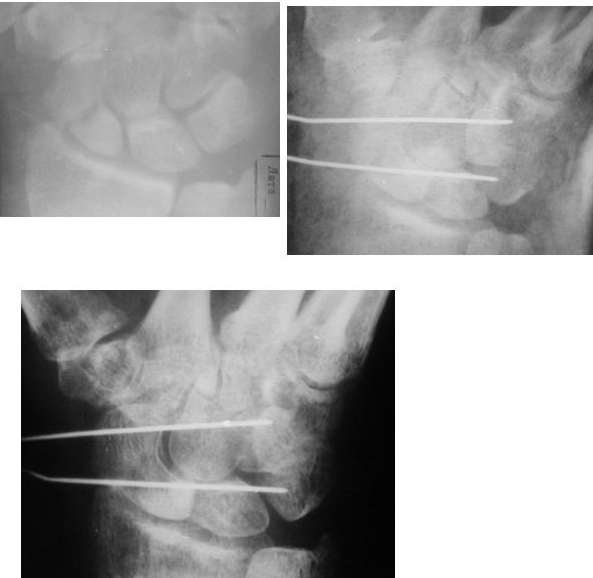

Re: Несращение ладьевидной кости после остеосинтеза компрессирущим винтом (nonunion of navicular bone after osteosynthesis with compression screw)

Боюсь, да - сращение не является результатом только фиксации, очень важно наличие кровообращения в стабильно фиксированых отломках. О механизме травмы общее представление мы получили, как питаются кости запястья знаем, да здесь вообще все может закончиться тотальным артродезом или эндопротезированием, а Вы о режиме думаете зачем-то. Это тоже важно конечно, если он до сих пор мотоциклист.

PS: ладьевидная кость является стабилизатором всех костей запястья, - она одна! Боль (субъективно) и нарушение функции (обьективно) по-другому преодалеть не удастся.